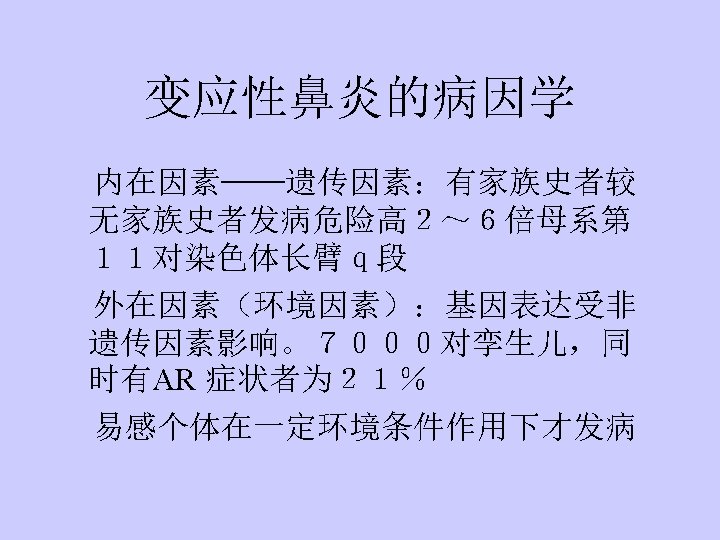

Nasal mucosal hyperreactive rhinopathy Allergic Rhinitis (AR) Perennial~(PAR), Seasonal~(SAR) (Pollinosis) Morbidity: 10%~20% Inhalant allergens——dust mite, house dust, pollen, fungi, animal danders, cockroach; Food allergens——milk, eggs, fish and shrimp, meat, vegetables, fruits.

Pathology: Type allergy Allergic inflammation: Predominant T cells & eosinophilic cells infiltrate.